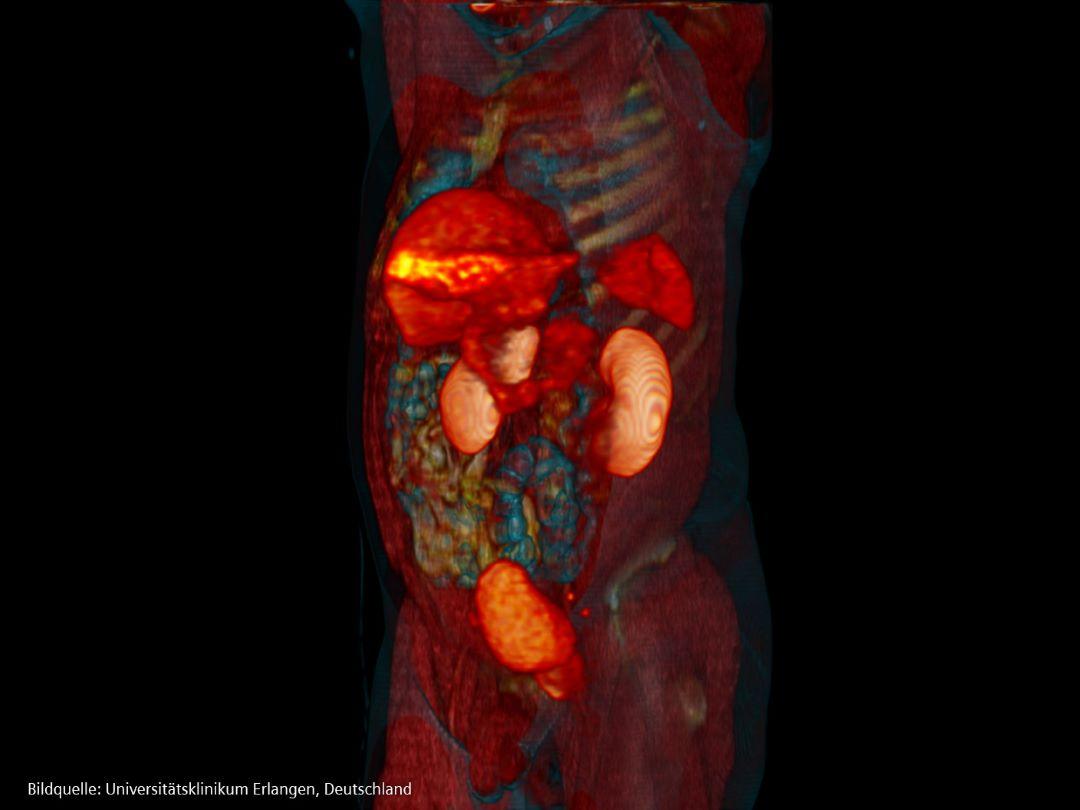

Theranostik revolutioniert die personalisierte Medizin durch den Einsatz von molekularer Bildgebung und Radioisotopen zur gezielten Bekämpfung der Krankheit. Die Behandlung von Prostatakrebs mit Theranostik bringt die personalisierte Medizin voran, indem die Krankheit mit individualisierter Präzision diagnostiziert und behandelt wird [23].

Bei der Theranostik setzen Ärzt*innen zunächst ein radioaktives Medikament ein, um Krebszellen zu lokalisieren und zu markieren. Wenn diese Radiotracer dem Patienten verabreicht werden, binden sie sich an bestimmte Moleküle oder Zellen, die mit der Krankheit in Verbindung stehen. Sobald die Tracer die Krankheit identifizieren, werden therapeutische Wirkstoffe – oft ebenfalls radioaktiv – verabreicht. Diese therapeutischen Wirkstoffe sind so konzipiert, dass sie die identifizierten kranken Zellen oder Gewebe gezielt angreifen und zerstören. Sowohl die diagnostischen als auch die therapeutischen Medikamente zielen auf das gleiche molekulare Ziel auf den Krebszellen ab und ermöglichen so einen präzisen Angriff, der die Behandlungsergebnisse verbessern und die Nebenwirkungen minimieren kann.

Zwei Aufnahmen: eine vor und eine nach der Behandlung PSMA PET/CT

Um sicherzustellen, dass Prostatakrebs nach der Behandlung wirklich verschwunden ist, bedarf es eines wachsamen und kontinuierlichen Überwachungs- und Pflegeprozesses. Der Eckpfeiler dieses Prozesses sind regelmäßige PSA-Tests, insbesondere in den kritischen ersten Jahren nach der Behandlung. Neben den PSA-Tests stützen sich die Ärzt*innen häufig auf körperliche Untersuchungen wie digitale rektale Untersuchungen und bildgebende Verfahren wie MRT, CT oder PSMA PET/CT, um nach Anzeichen zu suchen, die darauf hindeuten, dass der Krebs noch vorhanden sein könnte.